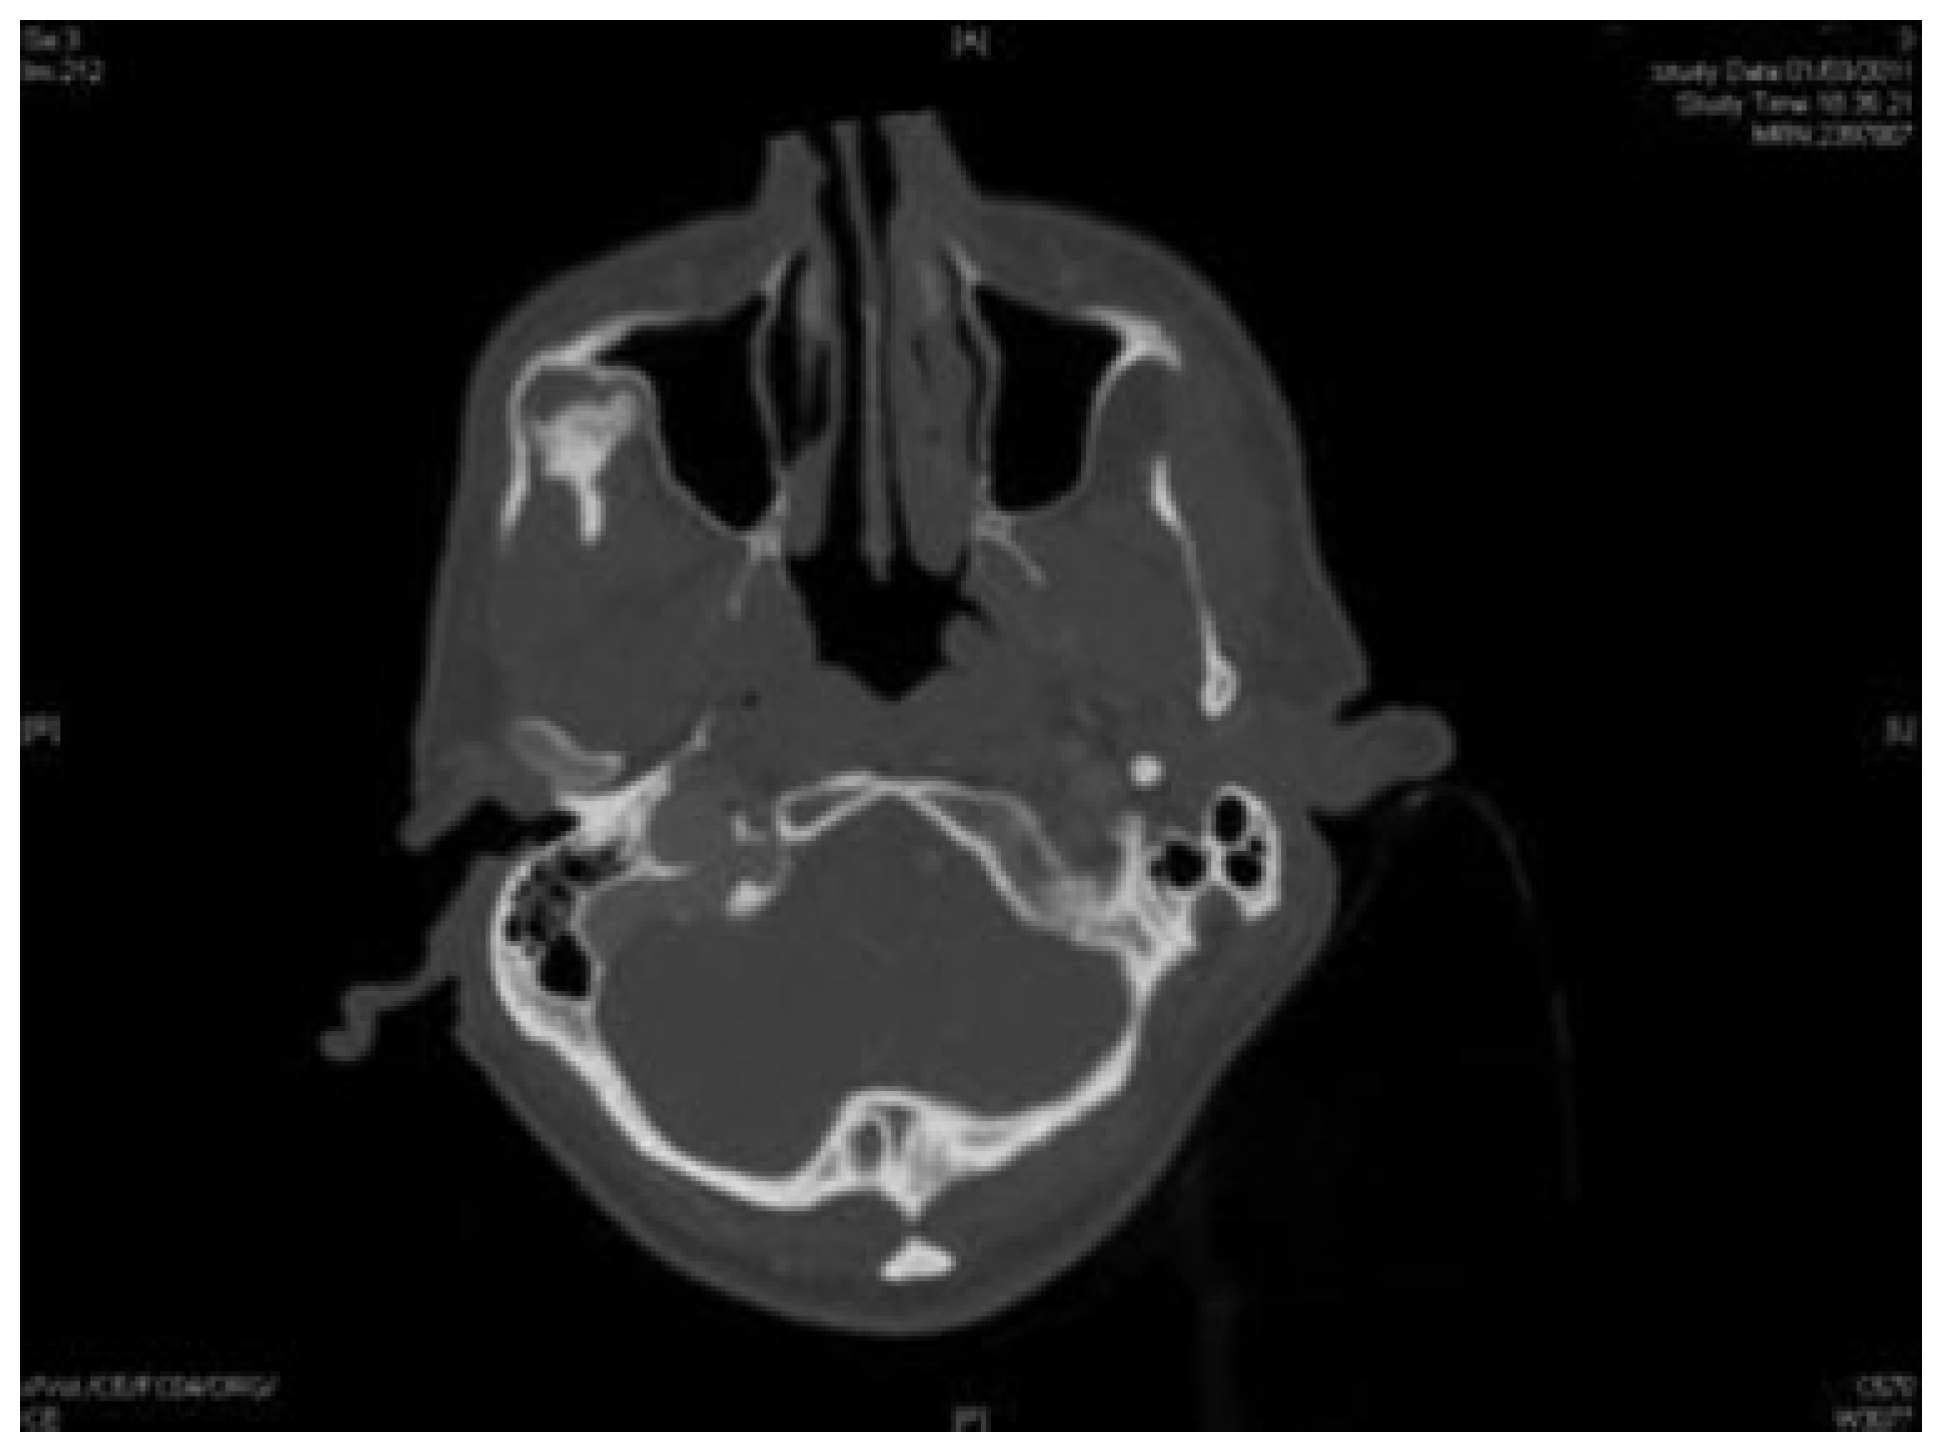

Osteochondroma of Coronoid Process: A Rare Etiology of Jacob Disease

Case Report